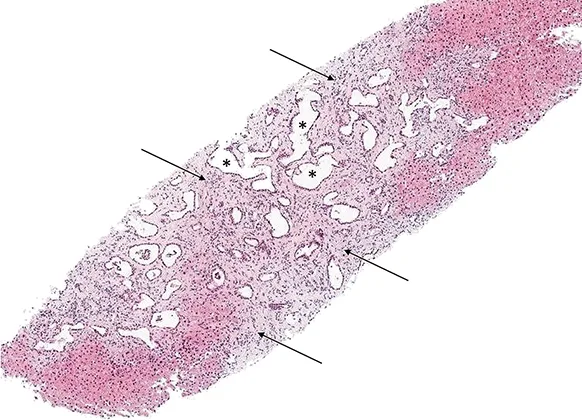

Figure 8 : Coupe histologique (coloration hématoxyline- éosine) d’une biopsie hépatique d’un patient atteint de fibrose hépatique congénitale : volumineux canaux biliaires ectasiques (étoiles) situés au sein d’une fibrose septale dense (flèches)

Contrairement à la maladie de Caroli, la biopsie hépatique est indispensable au diagnostic de FHC. Classiquement, l’histologie retrouve une fibrose septale dense avec présence en son sein de nombreux canaux biliaires de grande taille, ectasiques, communiquant avec le reste des voies biliaires (figure 8). En cas de syndrome de Caroli, les canaux biliaires ectasiques interlobulaires peuvent confluer en structures kystiques (17). Il existe également des anomalies vasculaires avec des veinules portes hypoplasiques. La préservation de l’architecture globale du lobule et l’absence de fibrose mutilante permet d’éliminer une cirrhose, qui reste le principal diagnostic différentiel histologique.